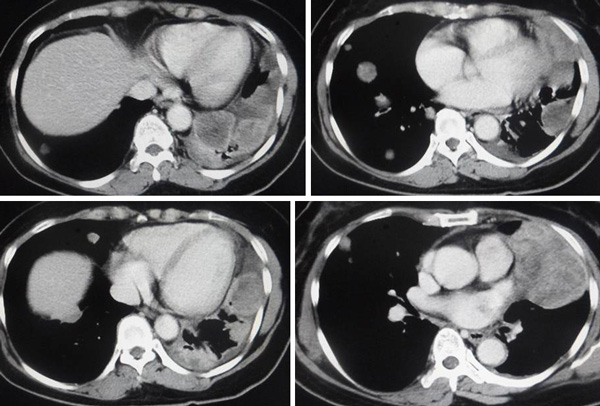

a) … do not allow your doctor to over-test your body with excessive amounts of radiation including excessive CAT scans or PET Scans, which can often make your condition worse by weakening your immune system (page 31),

b) … a single CAT Scan of the chest may be equivalent to 100 plain chest X-ray films and a PET scan performed with a radio-tagged sugar molecule may deliver 5 times the radiation dosage and exposure of a single CAT Scan(page 100),

c) The” gold standard” and most invasive testing is that of the PET Scan, which by radiological standards delivers as much radiation to the recipient as the entire combination of a head, chest, abdomen, pelvis and home scan combined (page 34),

d) The PET scan is based upon the fact that cancer cells, out of necessity rely upon simple sugars for this main source of nutrition. The scan itself uses a radio-tagged sugar molecule to essentially “light up” cancer anywhere in the body, except in the brain tissue which also rely upon sugar as its main source of energy. (page 34),

e) Incidentally, the PET scan is not definitive by any means. A cancer deposit or metastasis must reach a diameter between 5.0 and 10.0 mm before it can even be detected on a PET scan. Therefore, a sizeable amount of cancer could be present in the body and not be detected at all on PET scanning (page 35).